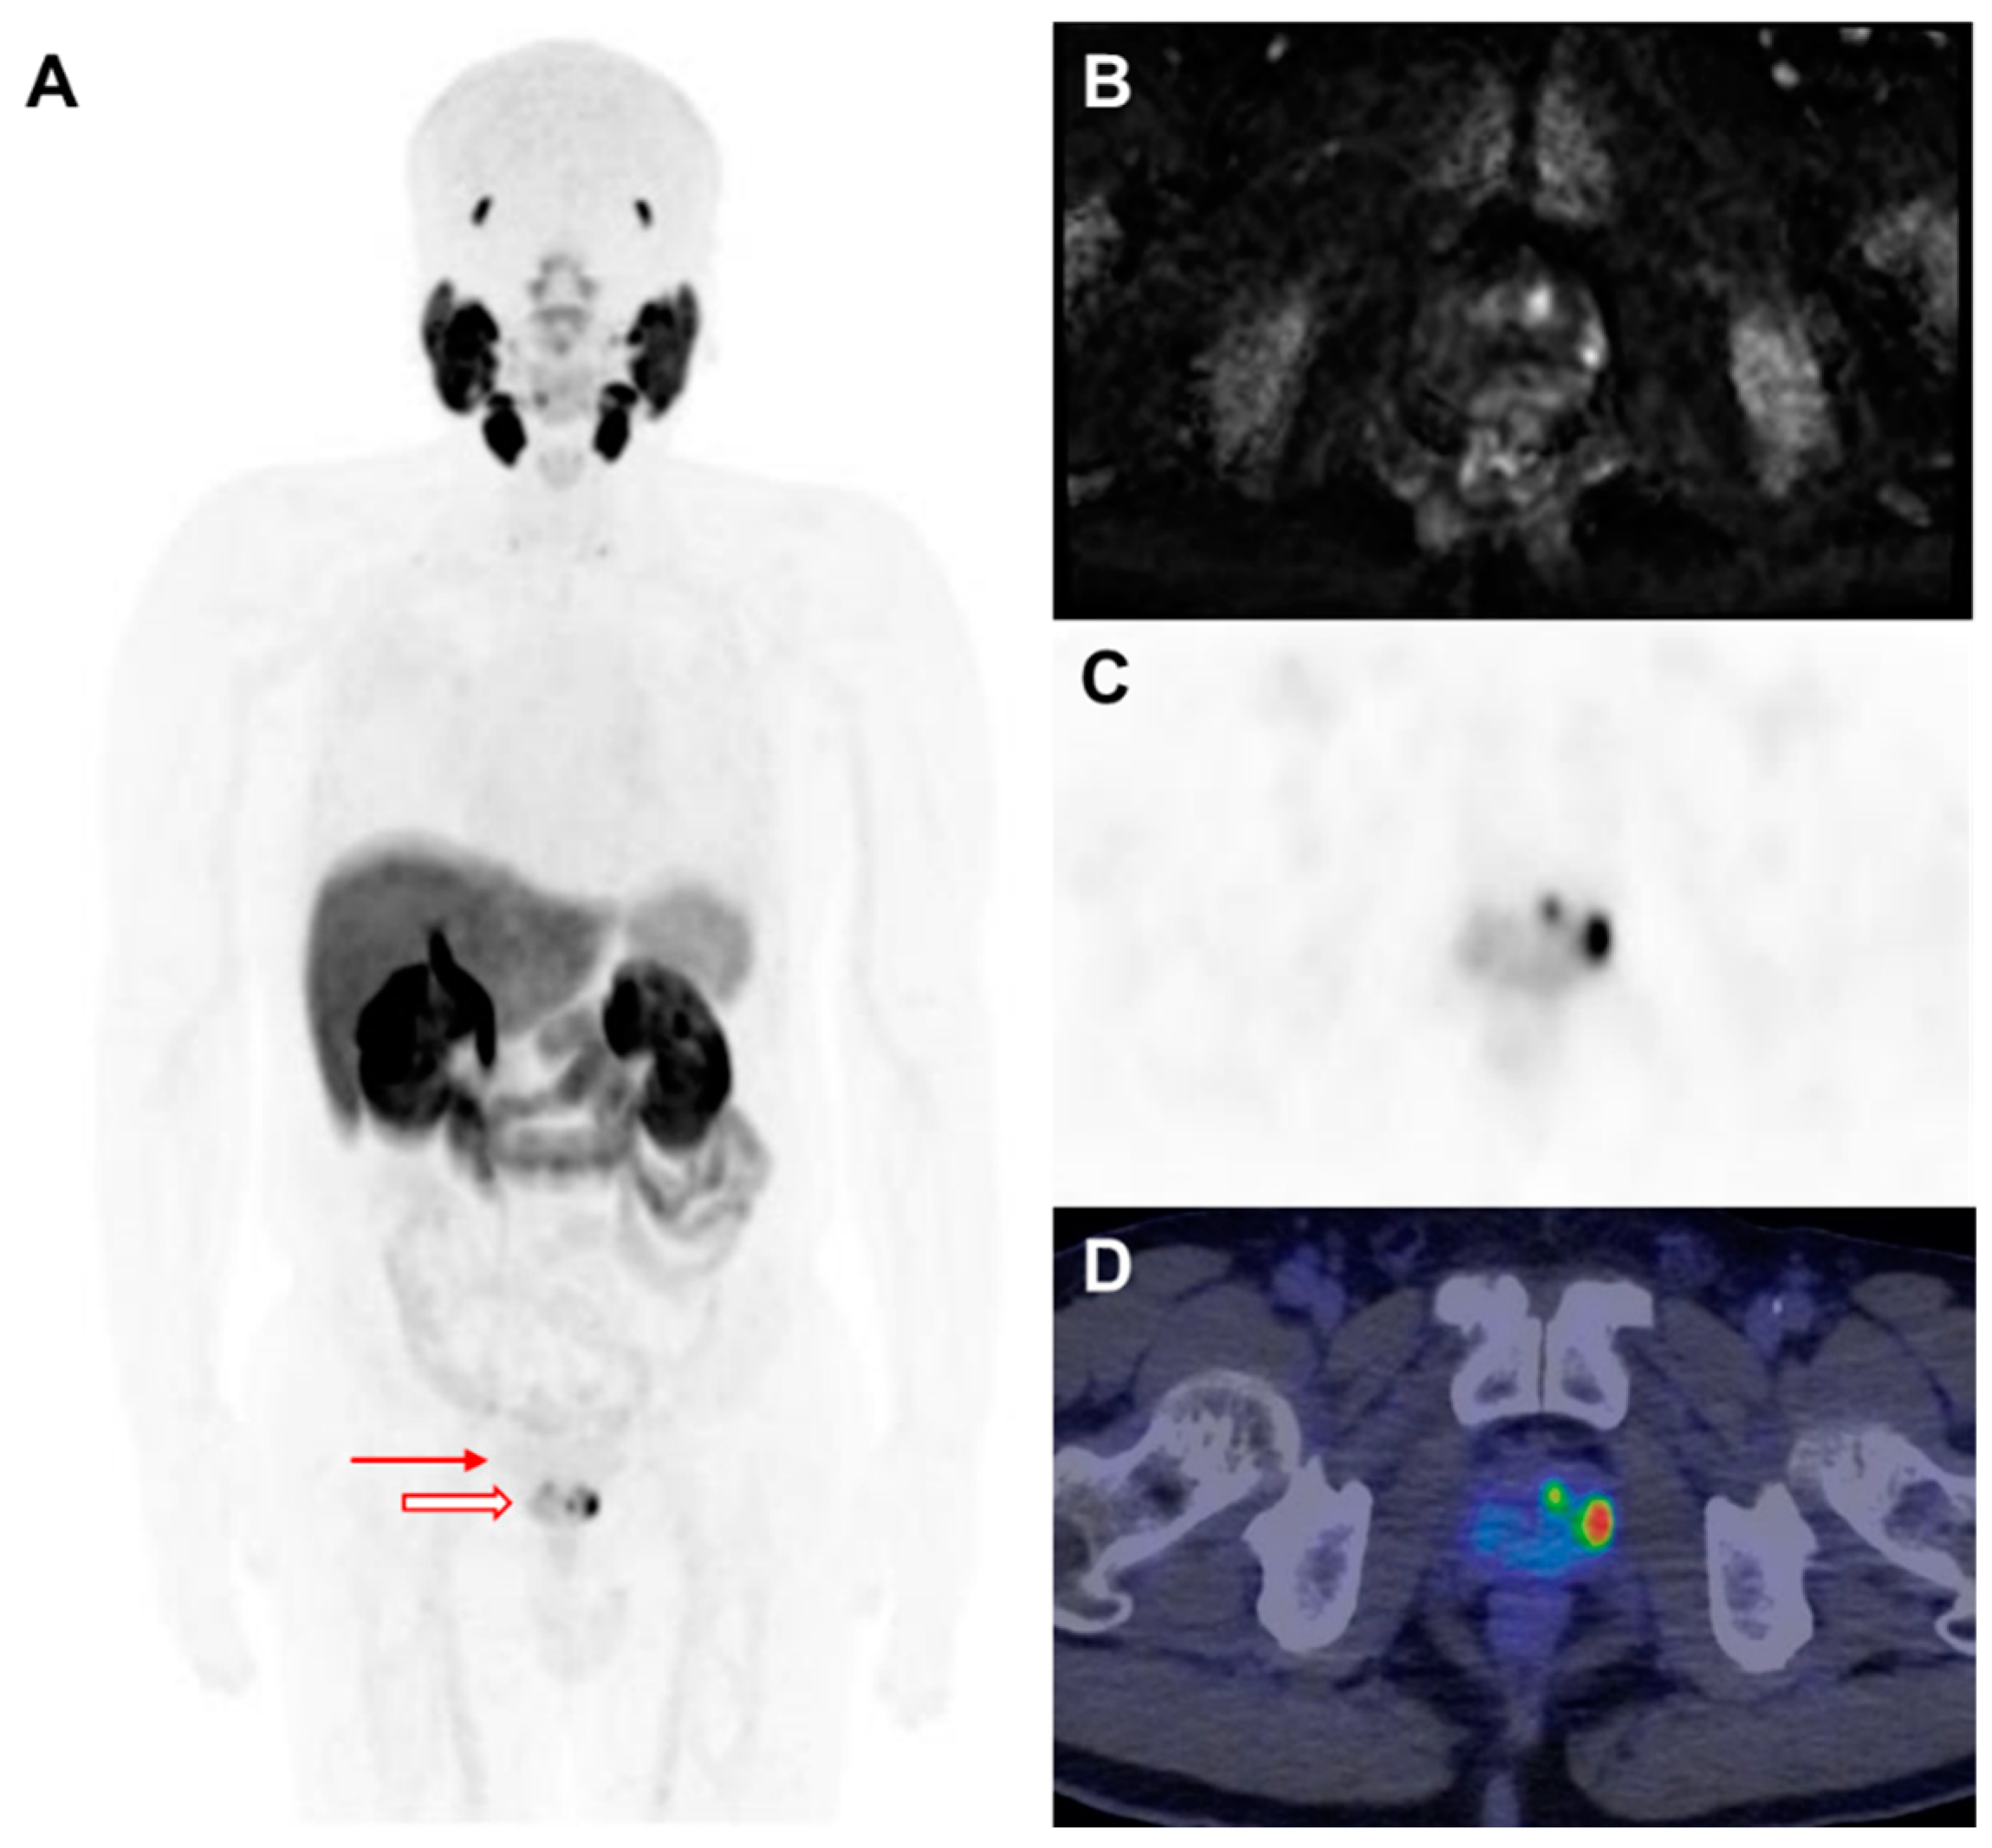

F-18-labeled radioligands have been investigated as alternatives to Ga-68-based agents, offering advantages, including greater availability and improved image resolution. F-18 DCFPyL has demonstrated a strong diagnostic performance in both the primary staging and restaging of PCa [52,53]. F-18 florastamin (F-18 FC303) is an emerging PSMA-targeted diagnostic radioligand that exhibits a higher tumor-to-background contrast as compared to F-18 DCFPyL, facilitating superior detection of osseous metastases, small metastatic lymph nodes, and primary tumors on delayed imaging [54]. Additionally, F-18 PSMA-1007 has been developed to minimize urinary excretion, enhancing the detection rates at lower PSA levels in both BCR and initial staging [42,55,56] (Figure 2). More recently, F-18 F-rhPSMA-7.3, which has received FDA approval, has been extensively evaluated and has demonstrated excellent diagnostic accuracy for nodal staging in intermediate- to high-risk PCa patients (Figure 3) [57].